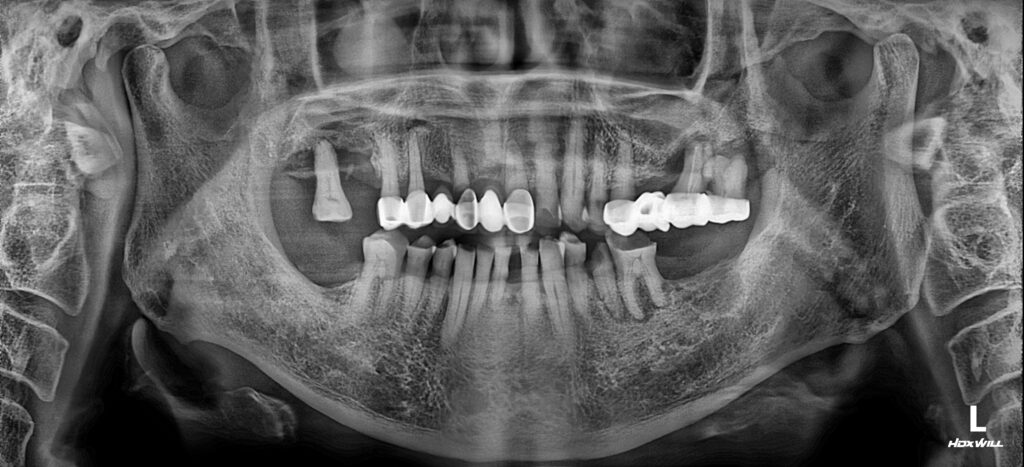

25.03.05

처음 내원하셨을 당시의 파노라마 방사선 사진입니다. 환자분께서 호소하신 왼쪽 아래는 이미 두 번째 어금니는 상실한 상태였으며, 앞에 있는 어금니와 작은 어금니들까지 깊은 치아우식과 치주질환으로 살리기 어려운 상태였습니다.

남포동임플란트 서울 화이트S치과는 4개의 임플란트를 식립함으로써, 상악의 치아들과 잘 맞물려 제대로된 식사를 하실 수 있도록 치료계획을 세워드렸습니다.